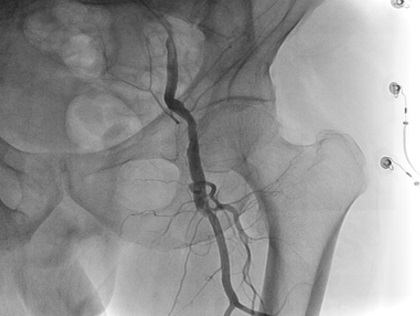

A 70-year-old gentleman with an extensive history of tobacco abuse and a non-ischemic cardiomyopathy presents with left leg claudication for the last 8 years.  His resting ABIs are right 1.00, left .80.  A 6F Ansel (Cook Medical) was selectively engaged into the common femoral artery and in spite of the fact that it was difficult to delineate the origin of the SFA, we passed the .014 Command wire (Abbott Vascular, Abbott Park, Illinois) with the CrossLock™ balloon catheter.  The FrontRunner™ was passed through the Rx port of the CrossLock™ and with the wire pulled back and the CrossLock™ balloon inflated, we were able to pass the FrontRunner™ across the total occlusion.  This was followed by balloon angioplasty and then multiple drug eluting balloons (Lutonix, Bard Peripheral, Tempe, Arizona).  Following this, there was excellent patency and runoff.

Figure 9. Total occlusion of the SFA.

Figure 10. Note the absence of a true origin treatment zone.